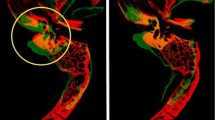

Advanced Normalization Tools software was used to construct a synthetic CT template from 6 subjects, and skull base structures were manually segmented to create a reference atlas. Landmark registration followed by Elastix deformable registration was applied to the template to register it to each of the 30 trusted reference image sets. Dice coefficient, average Hausdorff distance, and clinical usability scoring were used to compare the atlas segmentations to those of the trusted reference image sets.

The mean for average Hausdorff distance for all structures was less than 2 mm (mean for 95th percentile Hausdorff distance was less than 5 mm). For structures greater than 2.5 mL in volume, the average Dice coefficient was 0.73 (range 0.59–0.82), and for structures less than 2.5 mL in volume the Dice coefficient was less than 0.7. The usability scoring survey was completed by three experts, and all structures met the criteria for acceptable effort except for the foramen spinosum, rotundum, and carotid artery, which required more than minor corrections.

Currently available open-source algorithms, such as the Elastix deformable algorithm, can be used for automated atlas-based segmentation of skull base structures with acceptable clinical accuracy and minimal corrections with the use of the proposed atlas. The first publicly available CT template and anterior skull base segmentation atlas being released (available at this link: http://hdl.handle.net/1773/46259) with this paper will allow for general use of automated atlas-based segmentation of the skull base.